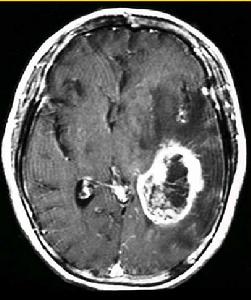

4.放射學檢查(1)顱骨X線片:岩骨平片見內耳道擴大、骨侵蝕或骨質吸收。(2)CT及MRI掃描:CT表現為瘤體呈等密度或低密度,少數呈高密度影像。腫瘤多為圓形或不規則形,位於內聽道口區,增強效應明顯。MRIT1加權像上呈略低或等信號,在T2加權像上呈高信號。第四腦室受壓變形,腦幹及小腦亦變形移位。注射造影劑後瘤實質部分明顯均一強化,囊變區不強化。

(3)CT及MRI檢查:目前聽神經鞘瘤診斷的標準是Gd-DTDA增強的MRI,特別是當腫瘤很小(<1cm)或在內聽道內,CT掃描陰性又高度懷疑腫瘤存在時應該進行GD-DTPA增強的MRI。CT與MRI兩種檢查有相輔相成的作用,如CT發現有病側內聽道擴大時,增強CT可發現腫瘤對於估計中顱窩入路時顳骨的氣化程度及高頸靜脈球與後半規管及底的距離有幫助。如果病人已作了CT而腫瘤較大,MRI可提供對腦幹壓迫的範圍Ⅳ腦室是否通暢腦積水、是否存在的情況對可疑聽神經鞘瘤或CT檢查難於確定時,全序列的MRI可做出鑑別診斷。但也要注意Gd-DTPA的可能假陽性,這與內聽道內神經的炎症或蛛網膜炎有關;任何小的接近底部的增強病變應該在六月後作MRI複查,以評估其生長情況。